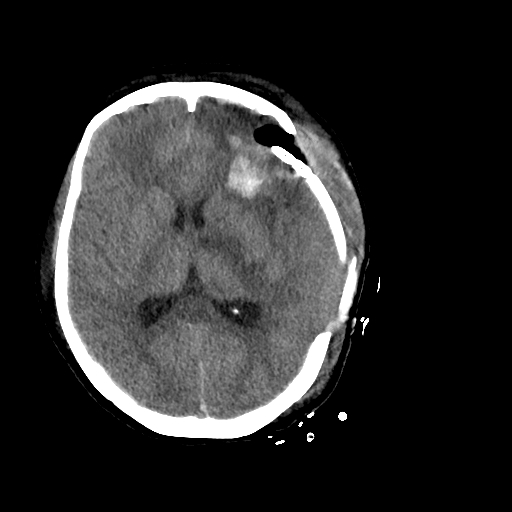

开颅手术于复合手术室进行。麻醉成功后,张锟会同刘耀东和神经外科副主任医师董雪涛,迅速完成开颅。医生们在显微镜下仔细操作,最大限度减少出血,初步快速清除硬膜下血肿及脑内血肿,为介入治疗赢得时间。与此同时,神经外科介入治疗团队副主任医师刘磊、主治医师段练与医师王绍珍迅速完成脑血管造影检查,发现左侧额叶脑血管畸形团,并成功进行了栓塞治疗。术后造影畸形血管团未再显影,随后由董雪涛及刘耀东继续完成血肿清除并去除骨瓣减压,术中出血200ml,最大程度上避免了出现因稀缺血型输血困难的问题。

额叶血肿清除术后,中线基本居中